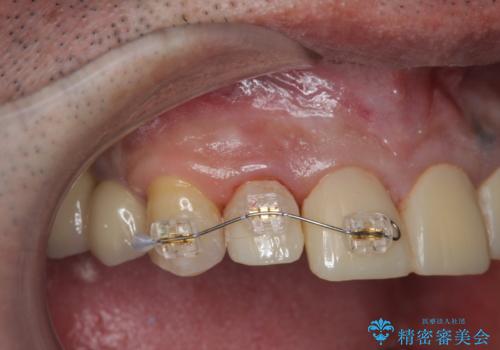

「 放置した虫歯 」 前歯セラミック治療

- 前歯の虫歯に気付きながらも放置し、一念発起し治療を希望され来院されました。

虫歯のマイクロスコープによる丁寧な除去、根管治療、深い虫歯に対する挺出(エクストリュージョン)および歯周外科を行ったのち精度の高いセラミッククラウン製作治療を計画します。

虫歯の放置により、根管治療や深い虫歯に対する処置が必要になりましたが丁寧に一つづつ処置を行ったことで抜歯をすることなく歯を残すことができました。

セラミッククラウンの製作をする前に、歯内・歯周環境の整備は非常に大切です。